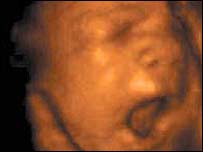

पंजाब में कुएँ में मिले कन्या भ्रूणों की ख़बर ने झकझोर कर रख दिया और बरबस ईरान की याद आ गई.

भारत में भ्रूण हत्या के मामलों में कमी नहीं

उन्होंने पूछा, क्या भारत में दहेज नहीं माँगा जाता और क्या वहाँ कन्या भ्रूण हत्याएँ नहीं होती? हमने जवाब तो दिया पर ये सवाल हमेशा के लिए दिल को झकझोर गया और फिर पंजाब की घटना ने इसकी याद दिला दी.

यानी सौ बात की एक बात आप 21वीं सदी के भारत की कोई भी तस्वीर पेश करें एक सच्चाई ये भी है कि कुछ चीज़ें आज भी हमें शर्मसार करती है.